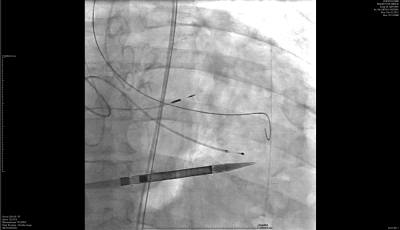

This minimally invasive procedure involves replacing a damaged aortic valve with a new one through a small incision in the groin, in most cases.

“When the aortic valve becomes very tight and doesn't open well, people experience being tired all the time, they have decreased energy, decreased exercise capacity, shortness of breath, chest pain, and then, more dangerously, may pass out,” Dr. Hyde said. “Most of the time, the diagnosis is suspected by symptoms and a loud murmur, but confirmation is made by an echocardiogram. The TAVR itself is where we go in the patient's groin, into the blood vessel and deploy a new valve inside their old valve that pushes the tight, stenotic valve out of the way, and then the new valve takes over.”